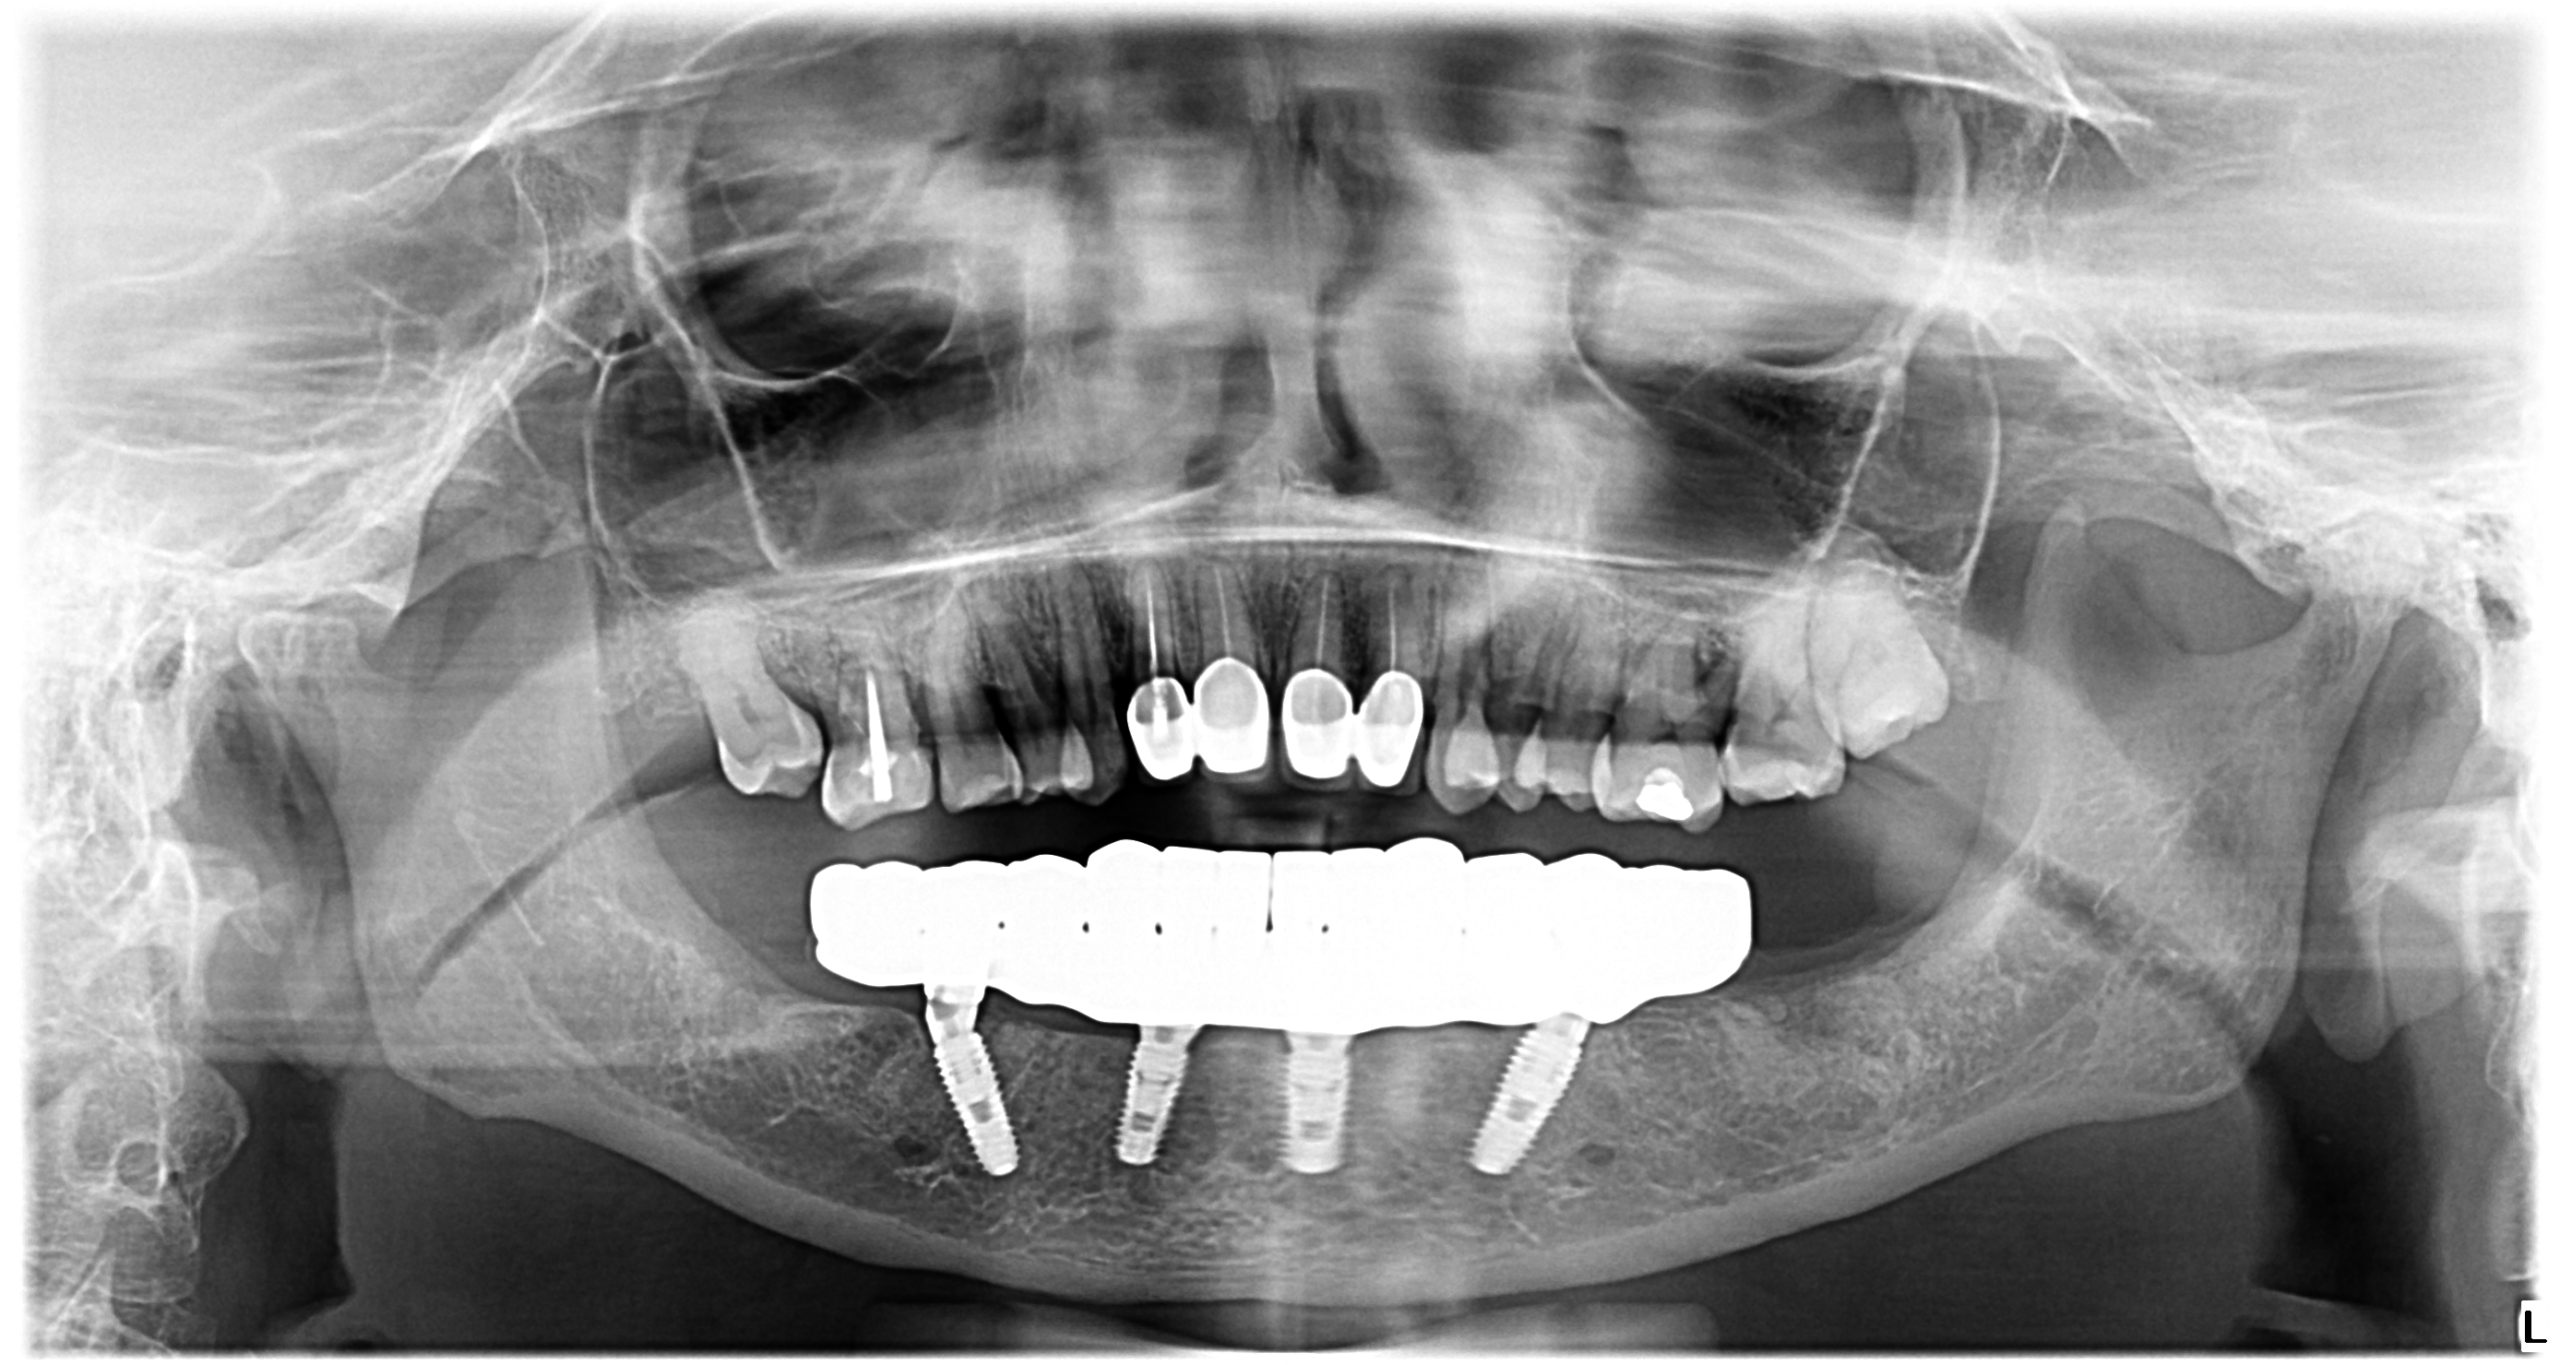

Există cazuri în care reabilităm doar o singură arcadă dentară. Este și cazul doamnei C. , care a benficiat de 4 implanturi dentare la mandibulă după ce boala parodontală i-a afectat partea de jos a danturii.

Atât în cazul unei singure arcade, cât și în cazul ambelor, reabilitarea orală constă în extragerea dinților care nu au putut fi salvați și înlocuirea acestora cu implanturi dentare. Doamna C. a primit o lucrare provizorie la 24h după inserarea implanturilor dentare, iar apoi o lucrare definitivă după 6 luni.